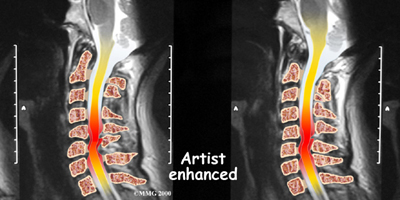

If more information is needed, your doctor may order an MRI. The MRI machine uses magnetic waves rather than x-rays to create pictures of the cervical spine in slices. MRIs show the cervical spine vertebrae, as well as the soft tissue structures, such as the discs, joints, and nerves. MRI scans are painless and don't require needles or dye. MRI scan has become the most common test to look at the cervical spine after x-rays have been taken.